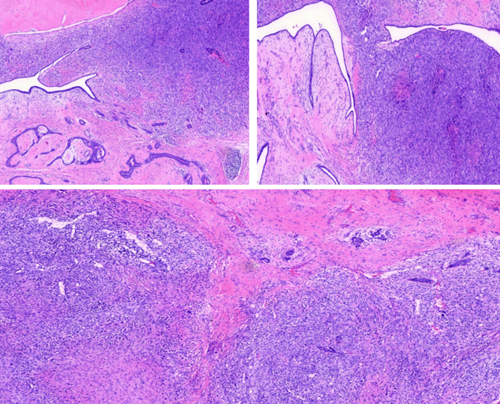

2.交界性叶状肿瘤:间质细胞有一定异型性,无过度生长,核分裂象增多,中度增生,生长更活跃,达不到诊断恶性标准。交界性有局部复发的潜在风险。

3.恶性叶状肿瘤:

■ 显著的间质细胞核异型性;

■ 间质过度生长(即1个4倍物镜x10倍目镜低倍视野不存在上皮成分);

■ 核分裂象增多(10/10HPF);

■ 间质弥漫富于细胞;

■ 浸润性边界。

符合上述所有条件,才能诊断为恶性叶状肿瘤。如出现恶性的异源性成分如脂肪肉瘤(高分化脂肪肉瘤不作为恶性标准)、骨肉瘤、软骨肉瘤、横纹肌肉瘤或血管肉瘤,则可直接诊断恶性叶状肿瘤,无需考虑其他指标。恶性具有局部复发风险,少数可远处转移(血行转移至肺、骨等)。当仅符合5要素中的部分诊断标准时,诊断为交界性叶状肿瘤。

(图:交界性叶状肿瘤,细胞较丰富密集)

(图:恶性叶状肿瘤,可见经典结构及恶性成分)